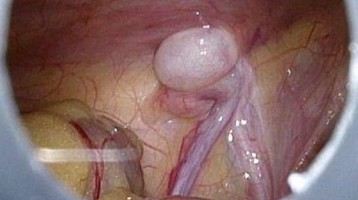

Sofortige Op. bei erworbenem Hodenhochstand nicht nötig

Wird bei Knaben ein erworbener Hodenhochstand erkannt, muss nicht gleich der Chirurg aktiv werden. Eine rasche Orchidopexie verbessert die Fruchtbarkeit nicht unbedingt.